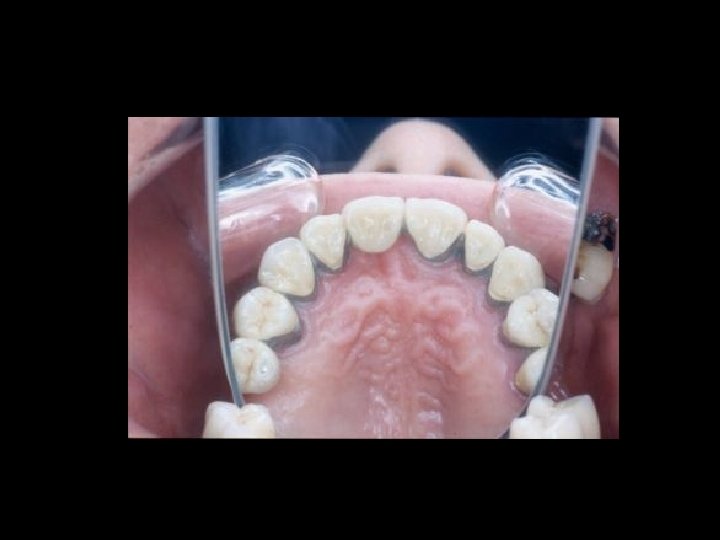

Responsabilità Garanzia di mezzi Ø Garanzia di risultato Ø Scelta del tipo di trattamento Ø Ø Condizioni denti Ø Condizioni delle mucose Ø Condizioni delle ATM Ø Preparazione dei denti pilastro Ø Prospettive di risultato estetico Ø Prospettive di risultato nel tempo Ø Caratteri del manufatto